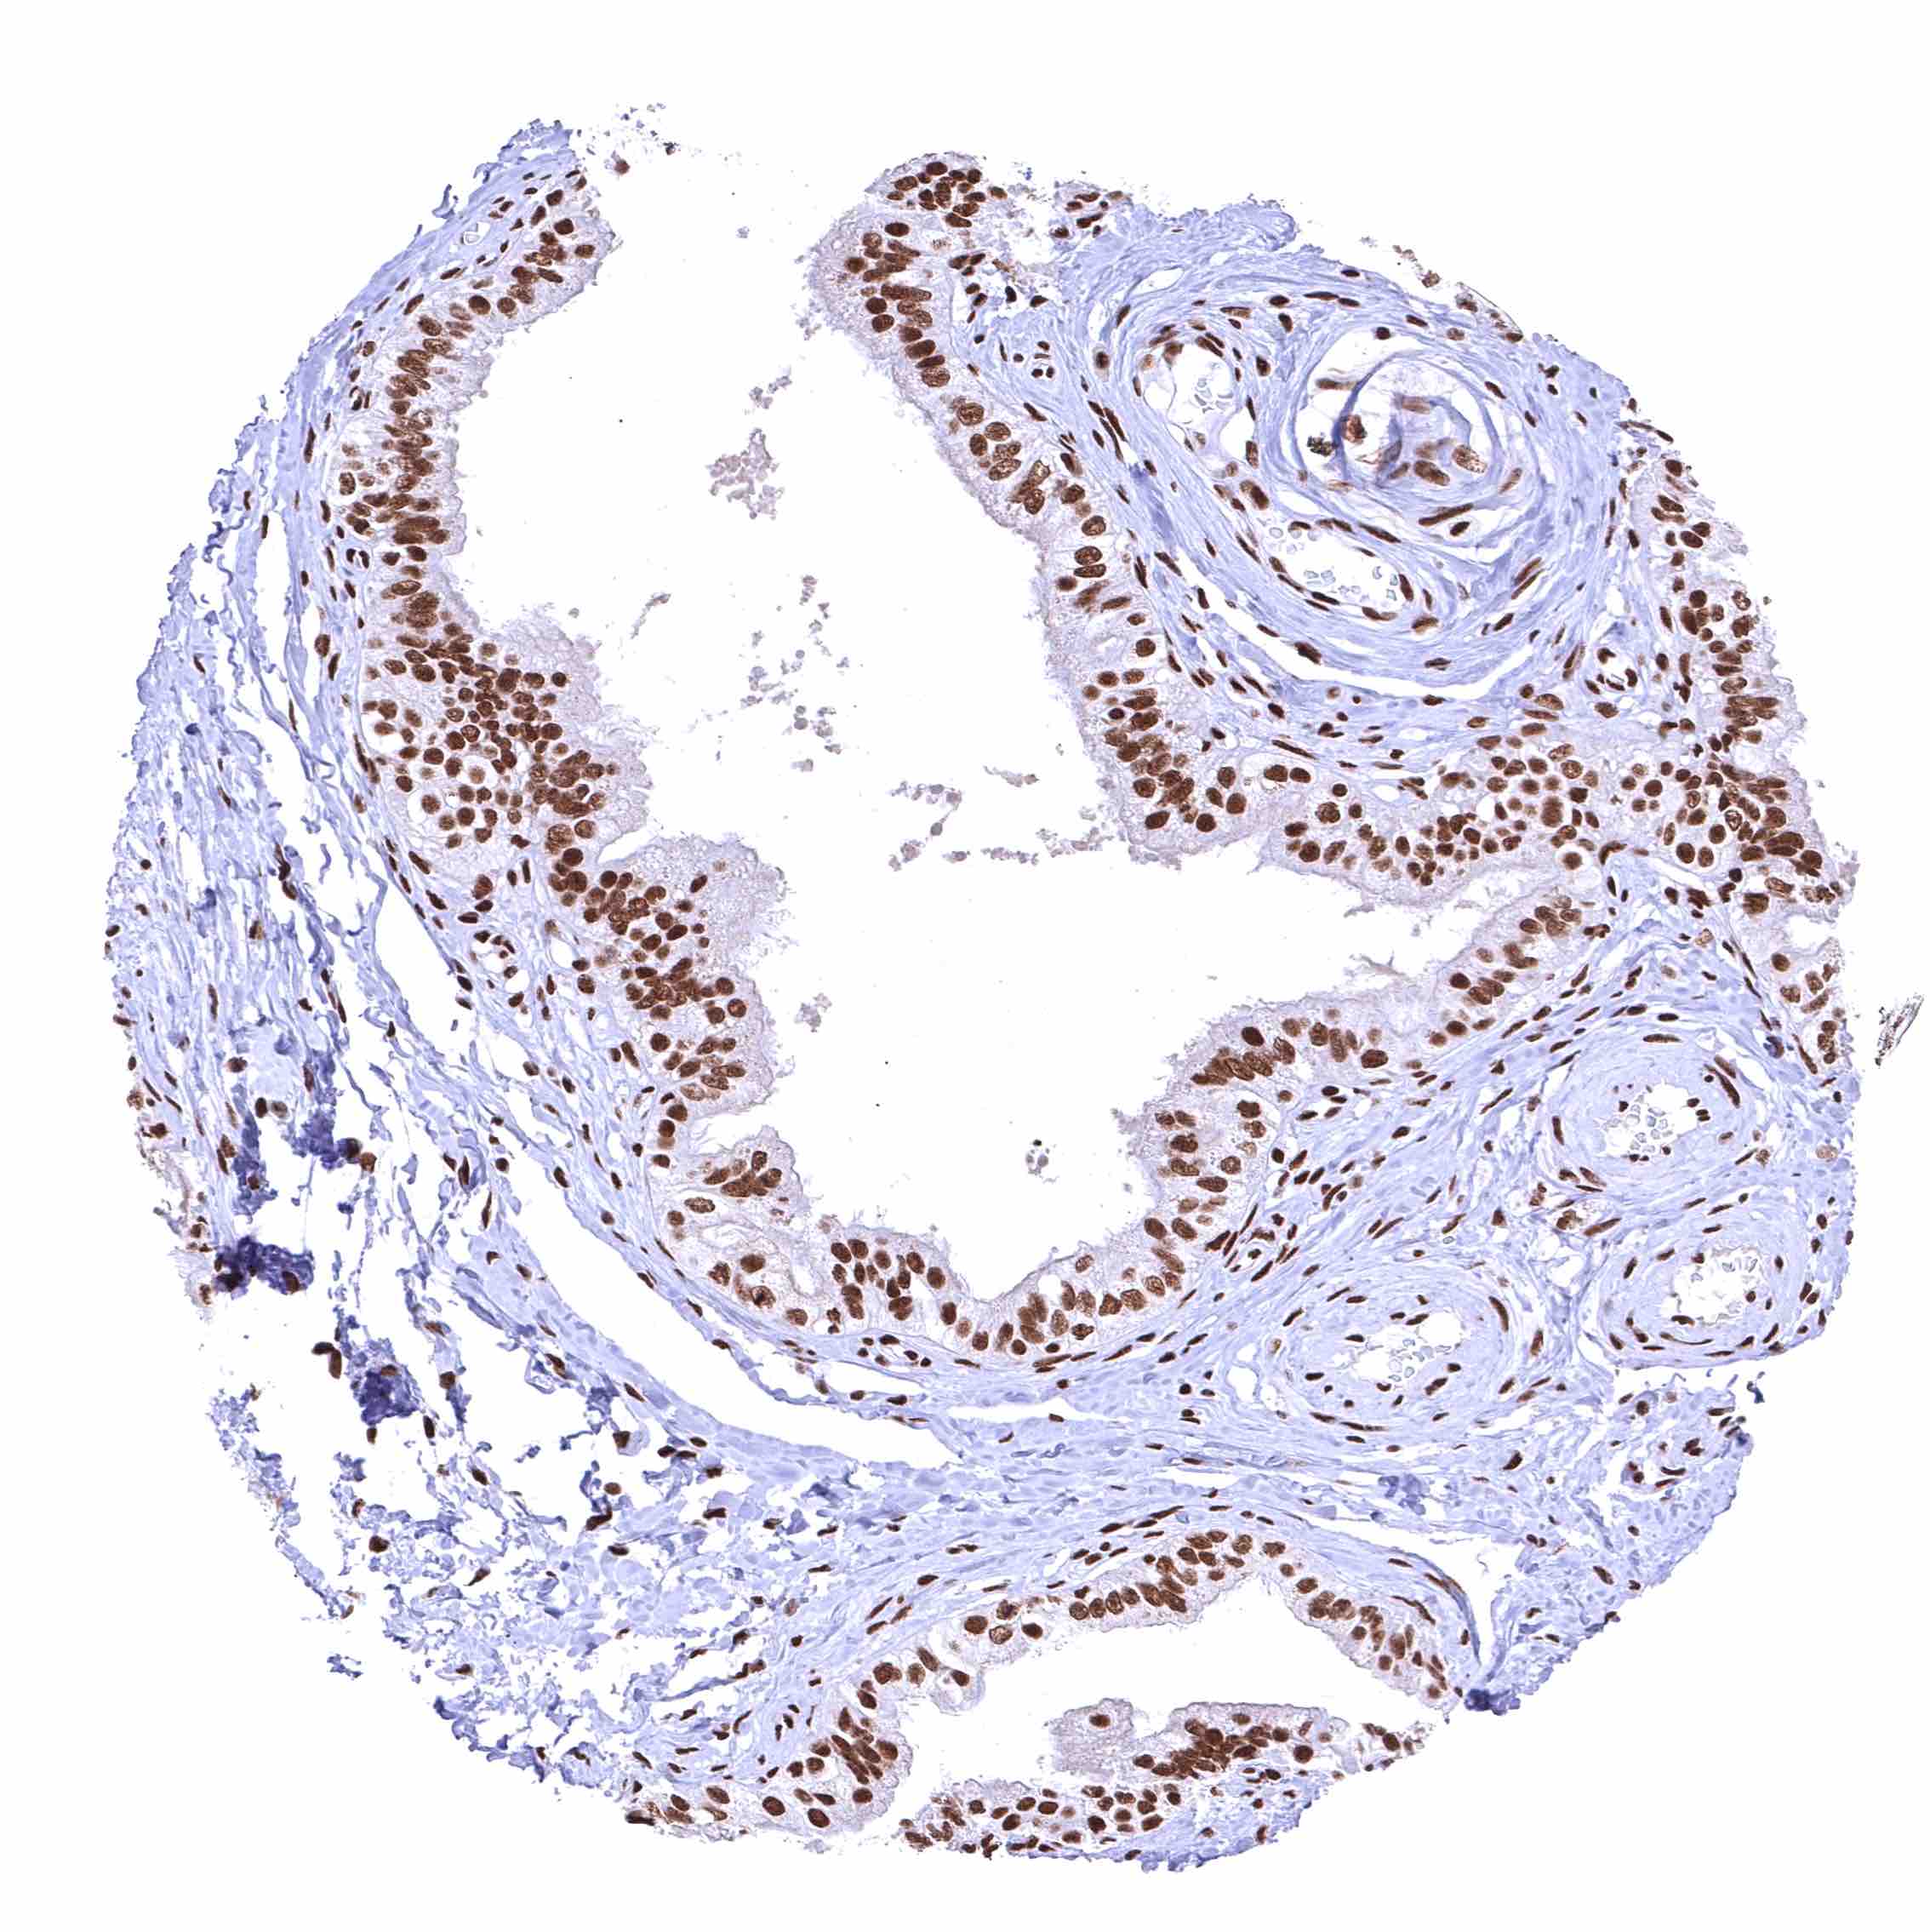

Skin – Strong nuclear BRD4 staining of squamous epithelial cells.

Skin, hairfollicel and sebaceous glands – Moderate to strong BRD4 staining of sebaceous gland cells. Nuclear BRD4 staining is somewhat stronger in associated hair follicles cells.